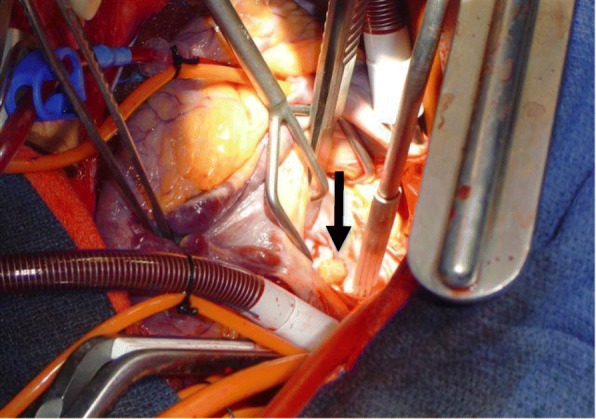

Fig. 3.

Intraoperative image: mitral valve myxoma. Arrow points to 2 × 3 cm

pedunculated, soft, and polypoid mass arising from posterior leaflet of mitral valve

A median sternotomy was performed and cardiopulmonary bypass was employed via aortic and bicaval cannulation with full anticoagulation. His aorta was cross-clamped and his heart arrested with retrograde cardioplegia. The aortic valve was examined through an ascending aortotomy and all three valve leaflets appeared normal. A left atriotomy was made and the mass was easily identified on the posterior mitral valve leaflet adjacent to the mitral valve annulus (Fig. 3). The mass was excised and a frozen section confirmed globular myxoma cells with abundant eosinophilic cytoplasm consistent with myxoma. The valve leaflet was reconstructed with an autologous pericardium patch and the annulus was supported using a running DeVega-type suture. The valve appeared normal and was tested; no regurgitation was noted. His left atrium and aorta were closed. His aorta was unclamped, after aggressive venting and de-airing maneuvers, and his heart returned to normal sinus rhythm with successful weaning from cardiopulmonary bypass. Anticoagulation was reversed with protamine and his chest was closed after placement of drains and pacing wires. At the conclusion of the operation, TEE confirmed appropriate mitral valve function and normal aortic valve with no evidence of a mass and no regurgitation at either location.